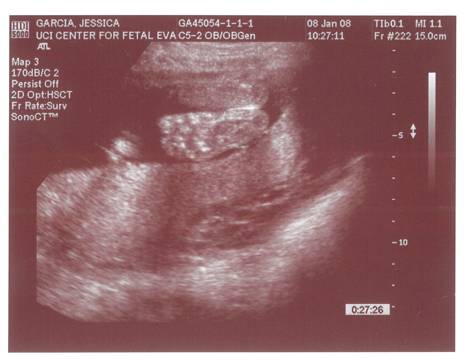

Babies First Pictures!!! ITS A BOY!

Yes we got a new dsmer coming into the world soon. We got our ultrasound today and its gonna be a boy. And shes a lot further along then we had originally thought. Shes due on April 15th which puts her at almost 6.5 months, (and really not showing it.) He weighs currently ~2lbs. He even opened his mouth while on camera which was really cool.

Here are the pics.

Pic 2: Mouth is open!